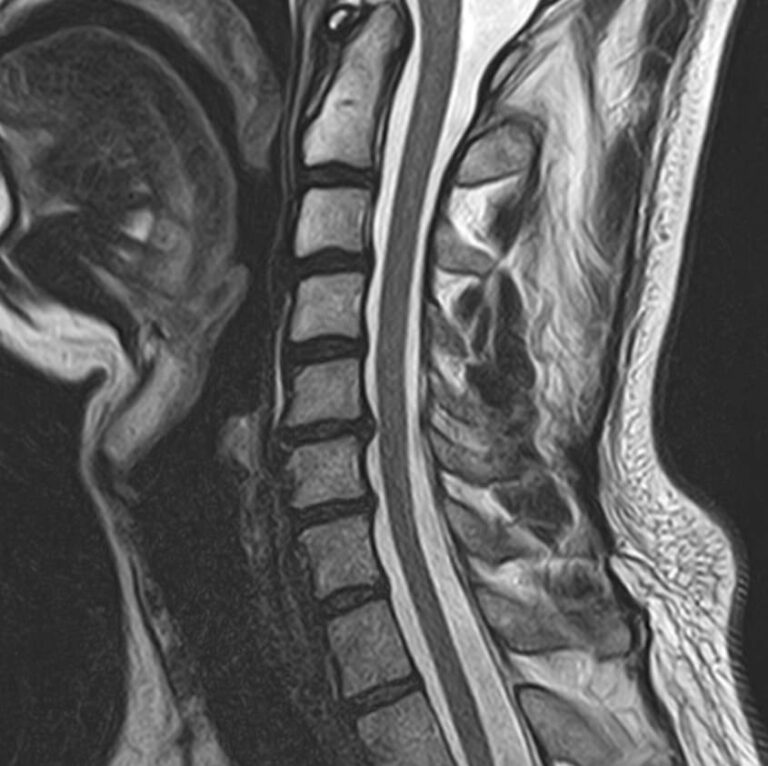

Магнитно-резонансная томография является современным, высокоинформативным и доступным методом обследования позвоночника. МРТ позволяет оценить состояние костных структур позвонков, спинного мозга, нервных корешков и окружающих мягких тканей.

В клинике «Доступная медицина» выполняется МРТ различных отделов позвоночника. В зависимости от уровня поражения можно провести МР томографию шейного отдела, грудного отдела, пояснично-крестцового отдела позвоночника и копчика.